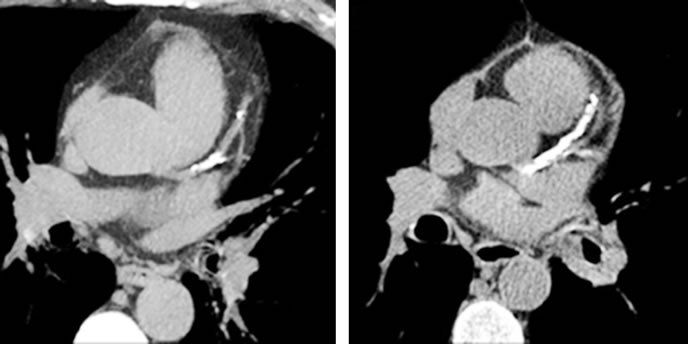

Calcium deposits in the arteries of your heart (coronary arteries) are often viewed as precursors to heart disease and a higher risk of heart attack because they can narrow the blood vessels. Coronary artery calcium (CAC) density screenings, though somewhat controversial and not appropriate for all patients, are sometimes used by doctors to assess an individuals risk for cardiovascular disease. But a recent Cleveland Clinic study suggests that greater coronary calcification may have at least one benefit. In the study, published in the Journal of the American College of Cardiology, researchers found that patients on aggressive statin therapy tended to see a reduction in arterial plaque volume while also experiencing greater calcification of that plaque.